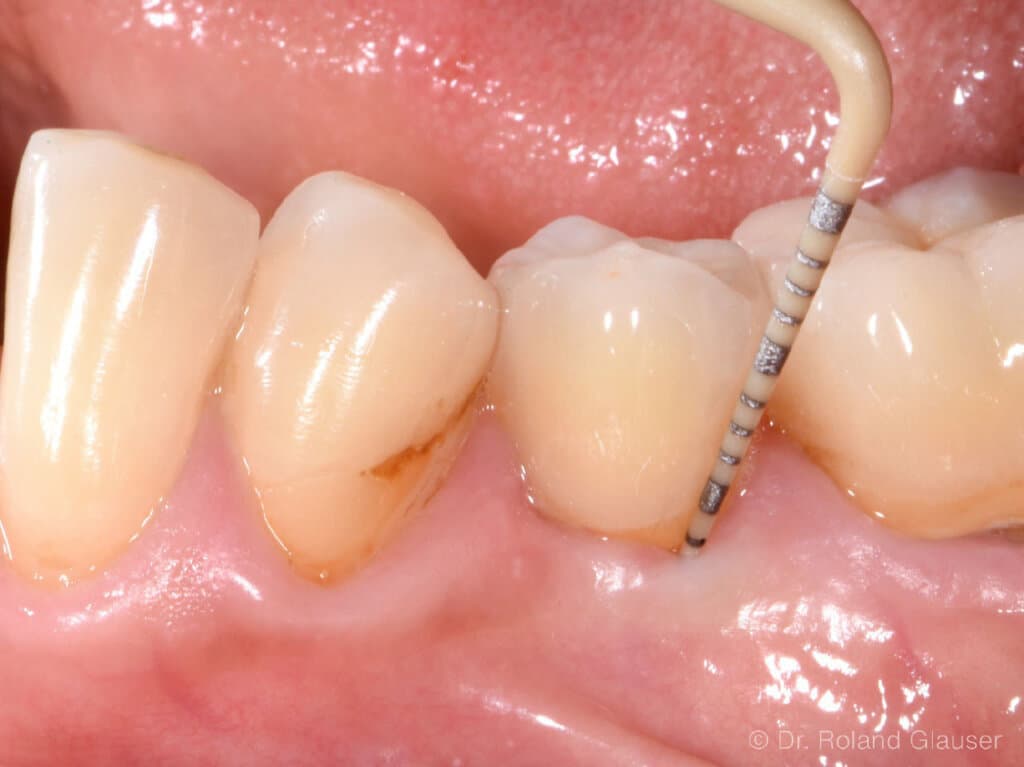

- Patent™ Symbionic Teeth zeigen nach 9 Jahren eine durchschnittliche Sondierungstiefe von 3 mm (entspricht dem Benchmark eines gesunden natürlichen Zahns; Abb. 4).1

Abb. 4: Ein Patent™ Symbionic Tooth nach 4,5 Jahren: Die maximale Sondierungstiefe von 3 mm entspricht dem physiologischen Zustand eines gesunden natürlichen Zahns.